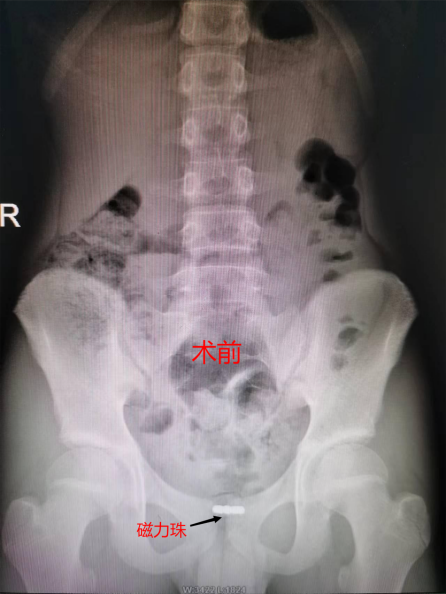

比如磁性球

图片